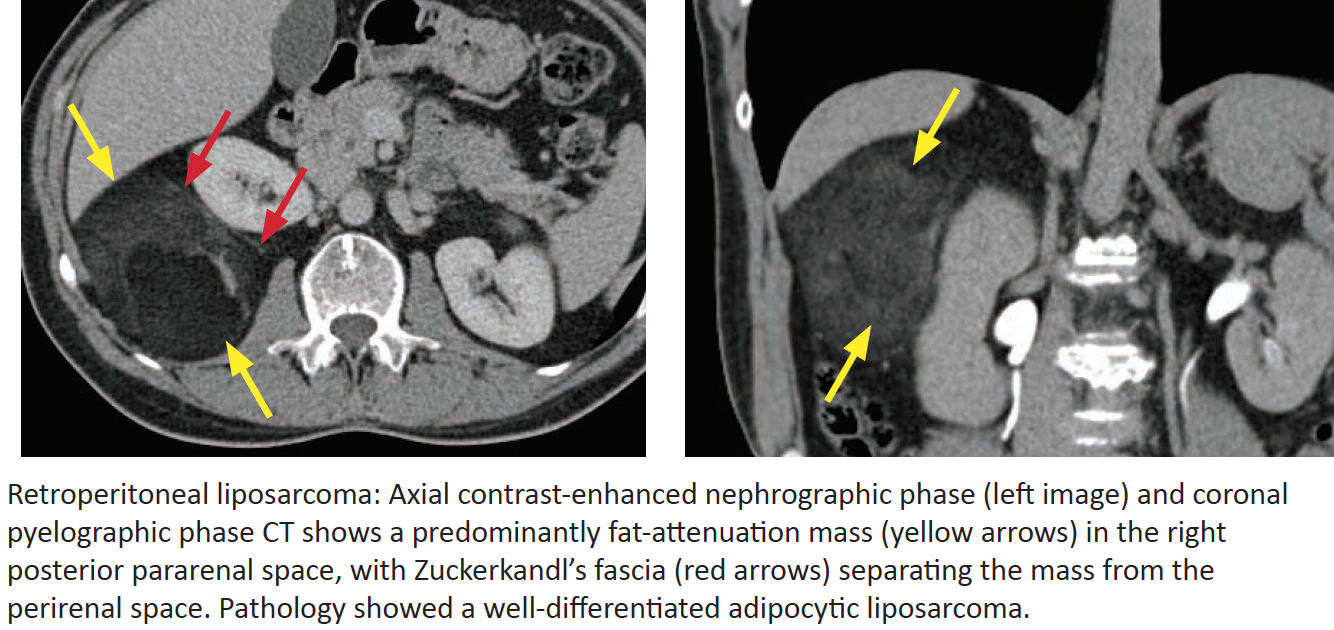

Liposarcoma

What are they? 10-15% arise from what area?

What is the most common subtype? Appearance?

In order of increasing malignancy, what are the other subtypes? The appearance of more malignant types?